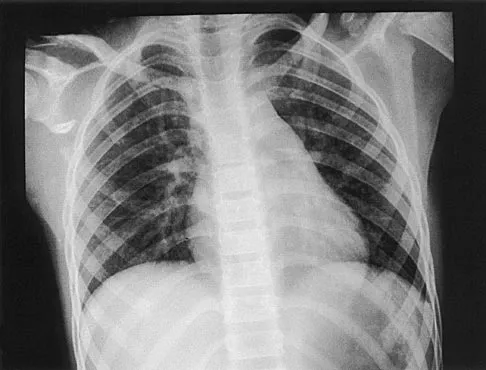

Question 32

A 12-year-old boy has severe left shoulder pain after being struck by an automobile. A chest radiograph, AP and lateral radiographs, and a CT scan with three-dimensional reconstruction of the scapula are shown in Figures 38a through 38d. Management should consist of